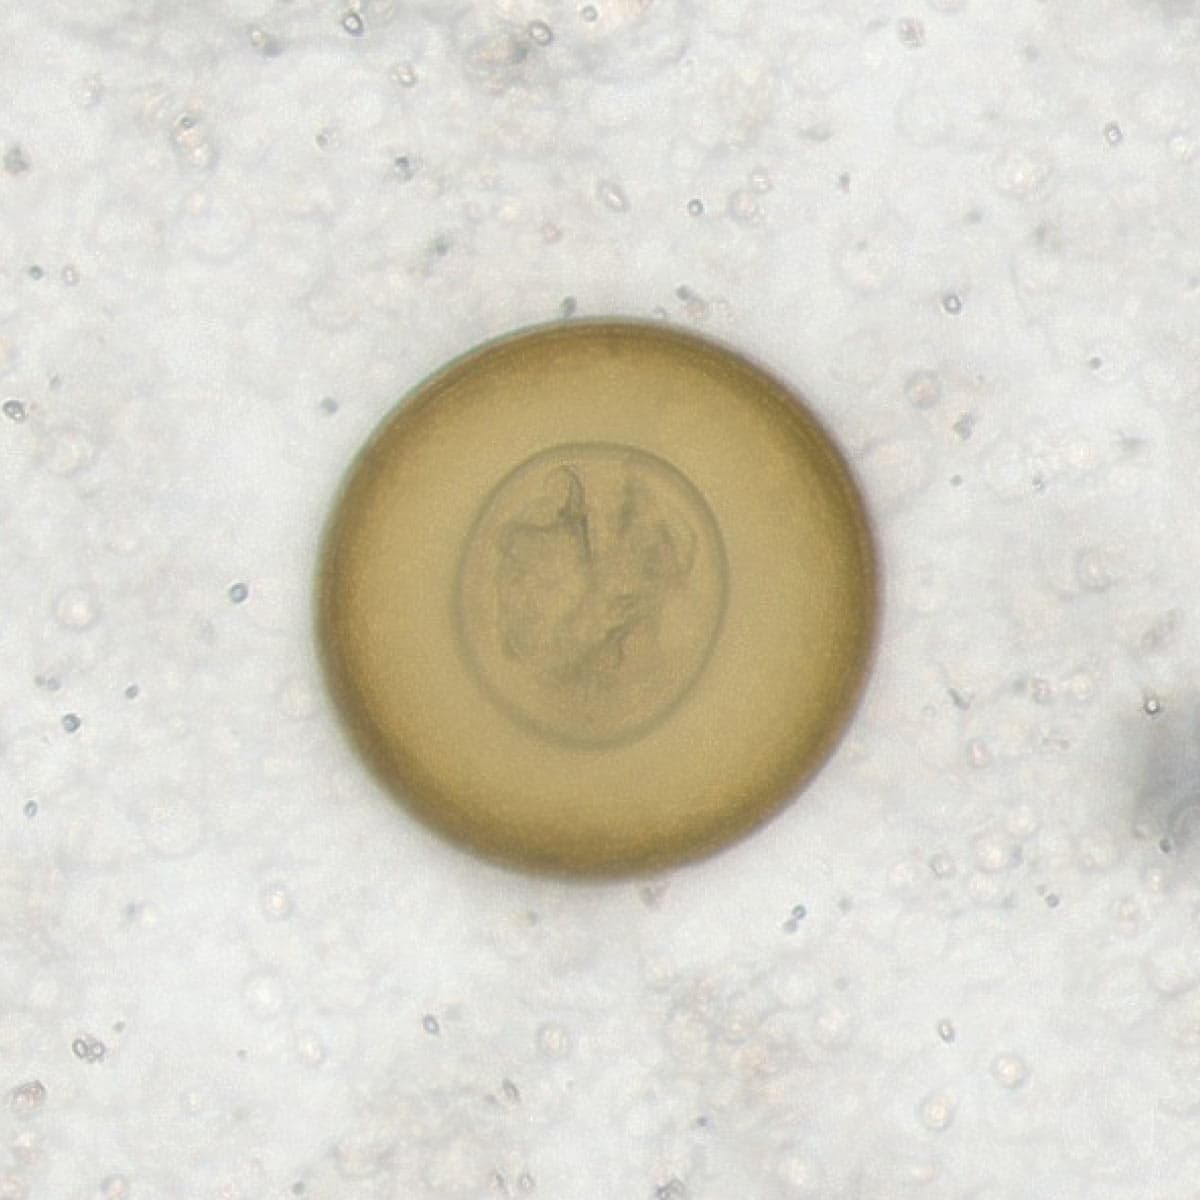

Automatic detection of rare species

Built on worldwide parasite-positive specimens, ParaScout AI identifies a vast number of parasite species, including those that are clinically rare or challenging to find.

Once the data is uploaded, the AI instantly identifies parasite species. You receive visual evidence for every finding, with dimensions to confirm the identification. Simply review the AI’s results and provide the final diagnostic confirmation.